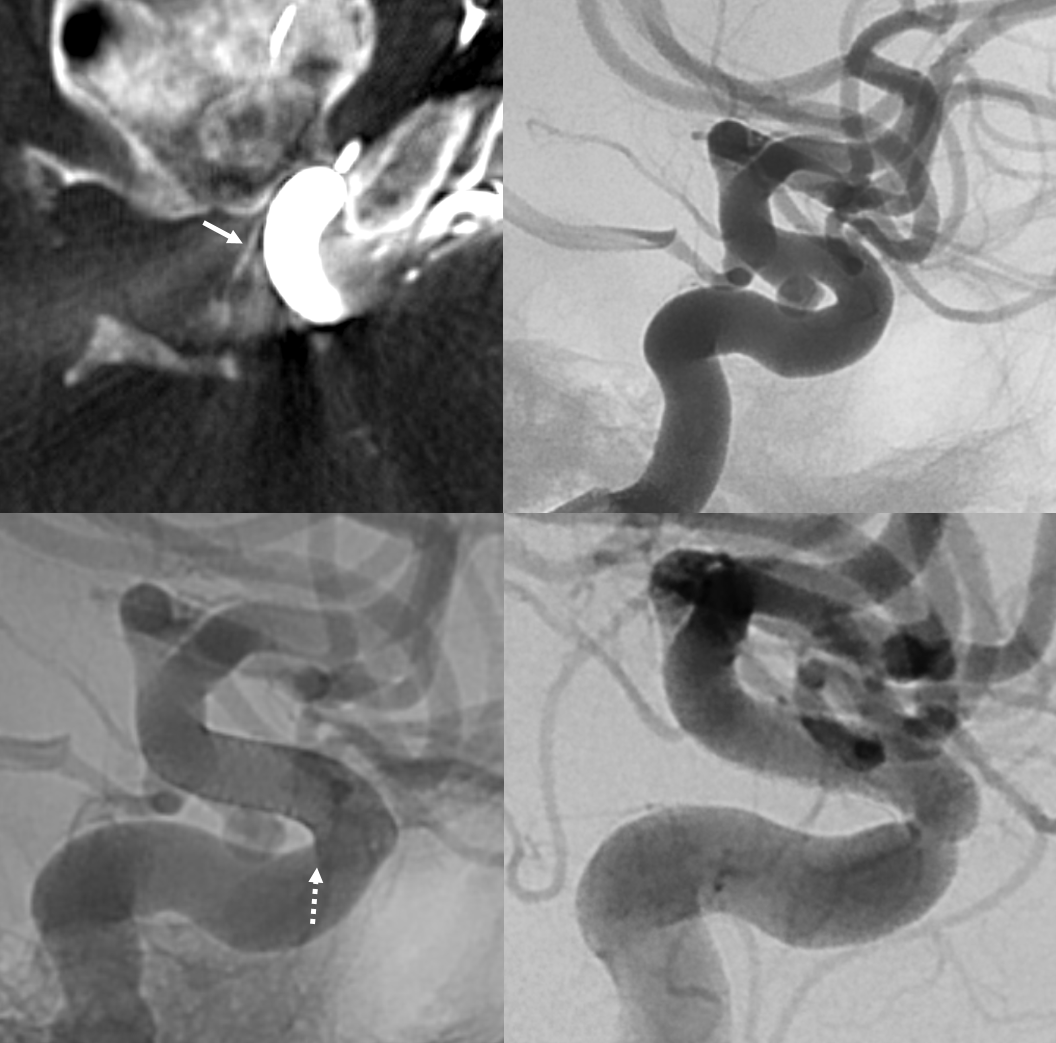

Another interesting topic. Courtesy Eytan Raz MD PhD. Hypophyseal Aneurysm, post PED

Follow up — notice a “lower” origin of the ophthalmic now, and a small vessel (arrow) from the medial wall, adjacent to the new ophthalmic ostium.

What happened to the ophthalmic origin? See Pipeline Device Properties page for more into. Basically, the Pipeline is not fully apposed to the ophthalmic ostium, creating a secondary communication between the aneurysm and the ophthalmic — essentially incorporating the ophthalmic ostium into the aneurysm. As the aneurysm shrinks, the flow to ophthalmic is reorganized. Other examples are on the Pipeline page.

Fine. But what about the little branch — the superior hypophyseal artery?

Whats interesting is that the superior hypophyseal was part of the aneurysm. Now that the aneurysm has shunk its ostium has come to appose the Pipeline, and its flow is preserved. Other interesting things are there too.

PCOM or Superior Hypophyseal? See below. We have all seen those “proximal PCOMs” Well, maybe not — could that really be a superior hypophyseal? Spectrum? Below is something that would normally be called a PCOM aneurysm

DYNA — dashed arrows point to a more proximal superior hypophyseal supplying the upper stalk. Then comes aneurysm and its bigger branch (open arrows) — a pseudo-PCOM if you will. It also contributes to supply of the lower pituitary stalk (solid arrows). The rest goes to the thalamus — as would a PCOM. There is no obvious connection to the PCA. Which is another curious question — when is a PCOM not a PCOM based on that. If you think these are irrelevant pontifications — they are not. Think of what is the territory at risk if this aneurysm is to be treated. And what is the best method? Coiling? Flow Diversion? Clip? Not so irrelevant anymore…

No labels

Another PCOM supply of pituitary — hypoplastic anterior superior hypophyseal branch (dashed arrow), PCOM (arrowhead) supply of pituitary and optic apparatus (arrows)

Largest PCOM supply — note very small classic location superior hypophyseal (dashed arrow). Large PCOM origin supply to pituitary (arrows). Note aneurysm (superior hypophyseal maybe?) and relatively distal origin of the ophthalmic

Posterior Pituitary Supply — MHT Balance

Excellent example of contralateral balance. On the left, there is a hypoplastic posterior hypophyseal network (part of MHT, arrowhead), and a prominent superior hypophyseal artery (associated with a small aneurysm). On the right, the opposite is true — large inferior hypophyseal arteries (dashed arrows) extending past midline due to contralateral hypoplasia, and a smaller superior hypophyseal, without aneurysm — not visible on these VRs, but seen on subsequent MIP images

MIP images — there is a small right superior hypophyseal artery present